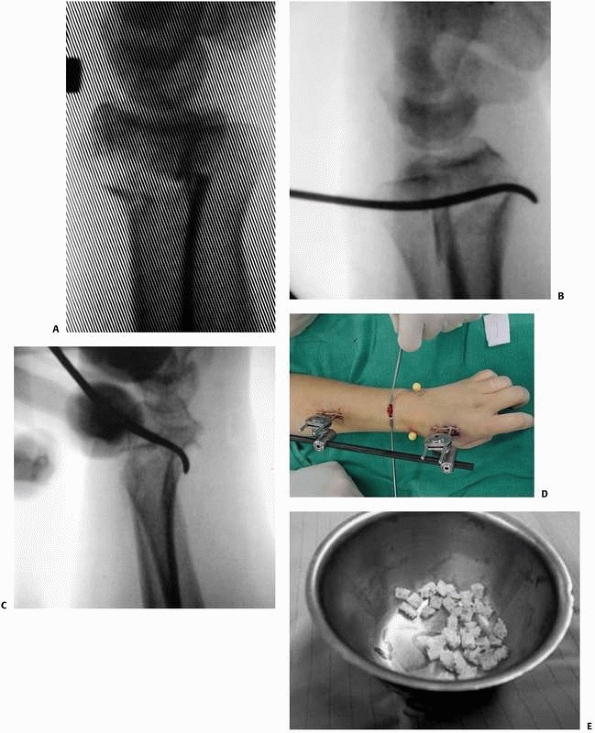

![]() |

FIGURE 30-21 Technique of percutaneous pinning of a dorsally comminuted metaphyseal fracture (A).

First the palmar cortex is re-approximated percutaneously using a curved Hohman retractor through an incision dorsally in the interval between the third and fourth dorsal compartments (B,C). The palmar tilt is restored and held with the fixator (D) and the subsequent metaphyseal defect is grafted using cancellous allograft (E). (continues) |

FIGURE 30-21 (continued) Finally, the lateral cortex is reduced with a percutaneously applied tenaculum clamp and crossed pins are inserted (F-H). The stability of the construct may be improved with the use of an additional pin applied radially (I).

|